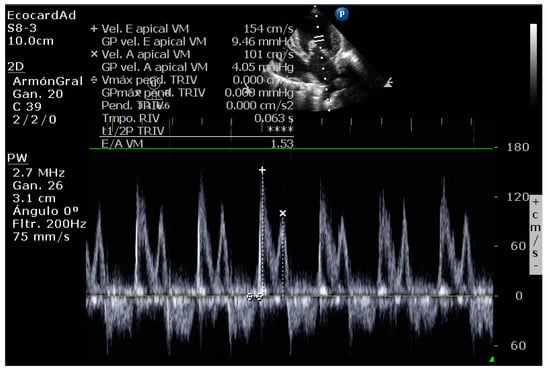

4.8.5. Vmax Wave E

4.8.6. E-Wave Deceleration Time

4.8.7. E/IVRT Ratio

4.8.8. E/é Ratio of the Mitral Annulus